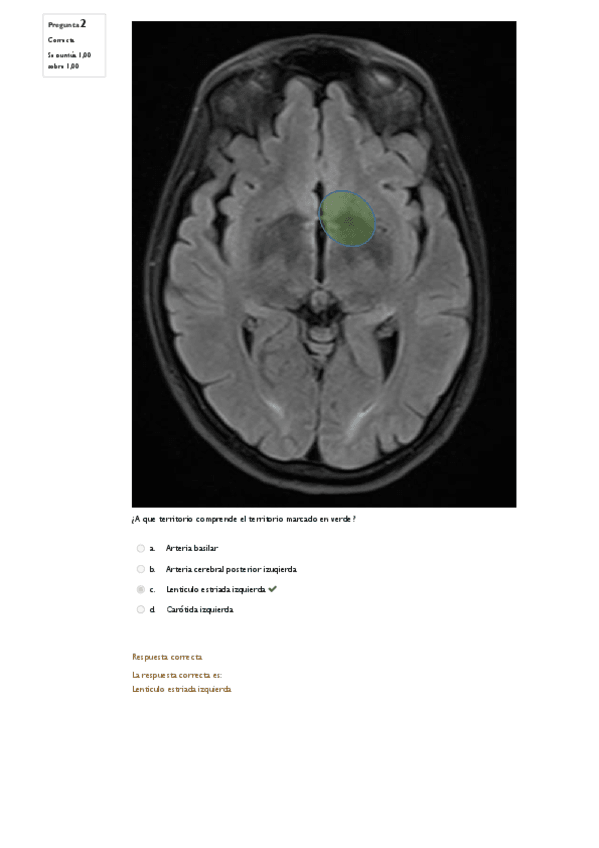

He publicado nuevos examenes de 4º Patología del Sistema Nervioso y Geriatría: EXAMEN-FINAL-NEURO-2023.pdf